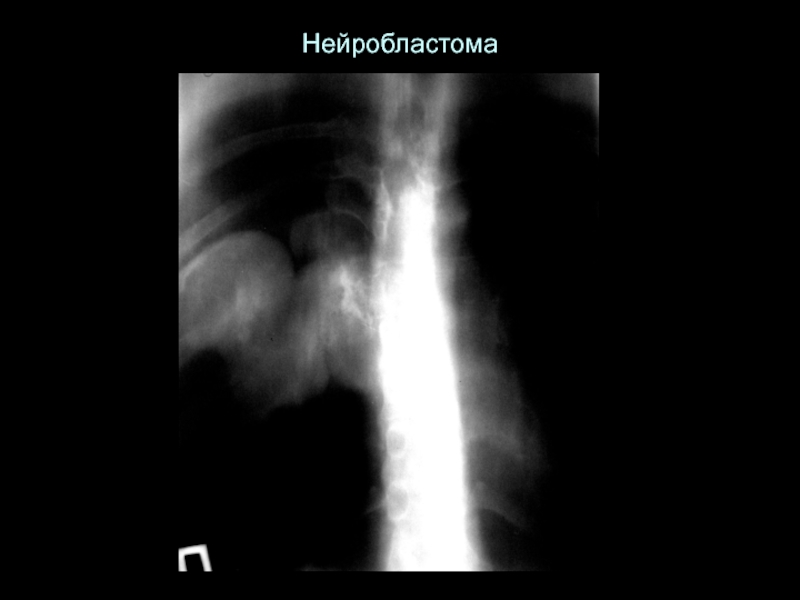

Слайд 33Нейробластома

Нейробластома

Слайд 47Нейробластома